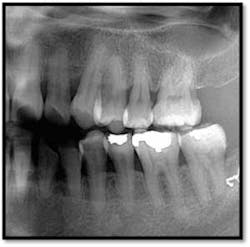

UL/LL reflected in a mirror and UL/LL radiograph

Treatment: FM Perioscopy completed in two, 2-hour sessions with local anesthetic and micro ultrasonics. No hand instruments are necessary during Perioscopy.